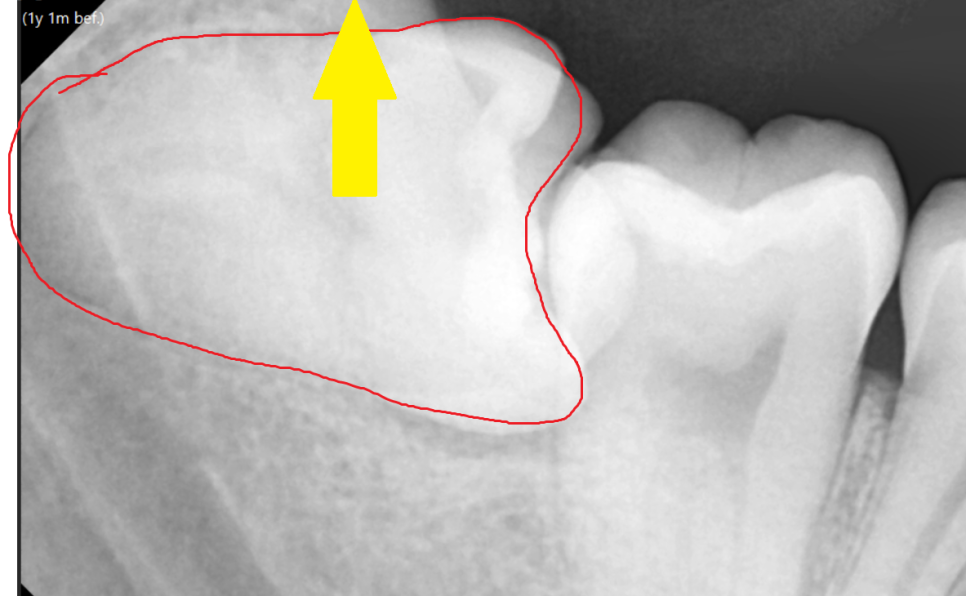

이렇게 누워서 난 사랑니는

수직으로 뽑을 수가 없기 때문에

쪼개서 뽑아야합니다.

발치 난이도도 올라가고

뼈도 삭제해야해서

발치 후 통증이 심할 수 있습니다.

해부학적으로 하치조 신경관과 근접하기 때문에

뽑고 나서 신경 손상 가능성도 있고요

그래서 꼭 ct를 찍어

안전한 상일동 사랑니 발치를 추구합니다.